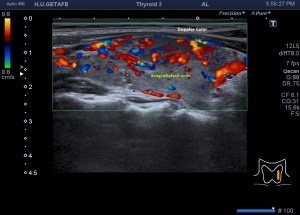

Cuando estudiamos concienzudamente la ecoarquitectura del Tiroides es momento de estudiar su apariencia vascular y descubro esto inmediatamente que me llama poderosamente la atención y que ves en la imagen 5, mira:

5

En la imagen 6 observas la misma imagen con el modo angio activado (doppler power), con el que vamos a conseguir observar la vascularización de flujo lento, por eso en el mismo corte puedes ver como si hubiera más vascularización que ves en la imagen 5.

6

En la imagen 7 tienes el corte del lado contralateral del tiroides, donde con el modo angio activado, puedes ver además que ese lóbulo tiene más actividad vascular que el izquierdo.

7

En conclusión, con esta vascularización (infierno tiroideo), el aspecto general de la glándula y la información clínica detallada del informe radiólogico, y por supuesto, pruebas analíticas (hipertiroidimo), otras pruebas imágenes y la historia clínica (taquicardias) detallada de la que disponía la endocrina al cargo de la paciente, se diagnosticó una Enfermedad de Graves-Basedow.